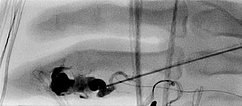

Fluoroskopische Darstellung der Punktionsnadel bei Beginn der direkten perkutanen Embolisationstherapie am Finger mit einem Flüssigembolisat (EVOH). Zusätzlich sichtbar der nicht ganz bis zum Nidus vorgeschobene Mikrokatheter.

Fluoroskopische Abschlußkontrolle nach erfolgreicher Nidusembolisation der AVM. Der transarteriell von brachial eingebrachte Mikrokatheter wurde während der perkutanen Embolisation als Landmarke für die zuführende Arteria digitalis propria belassen. Zusätzlich sichtbar röntgendichte Markierungen durch auf der Haut aufliegende Kompressen.